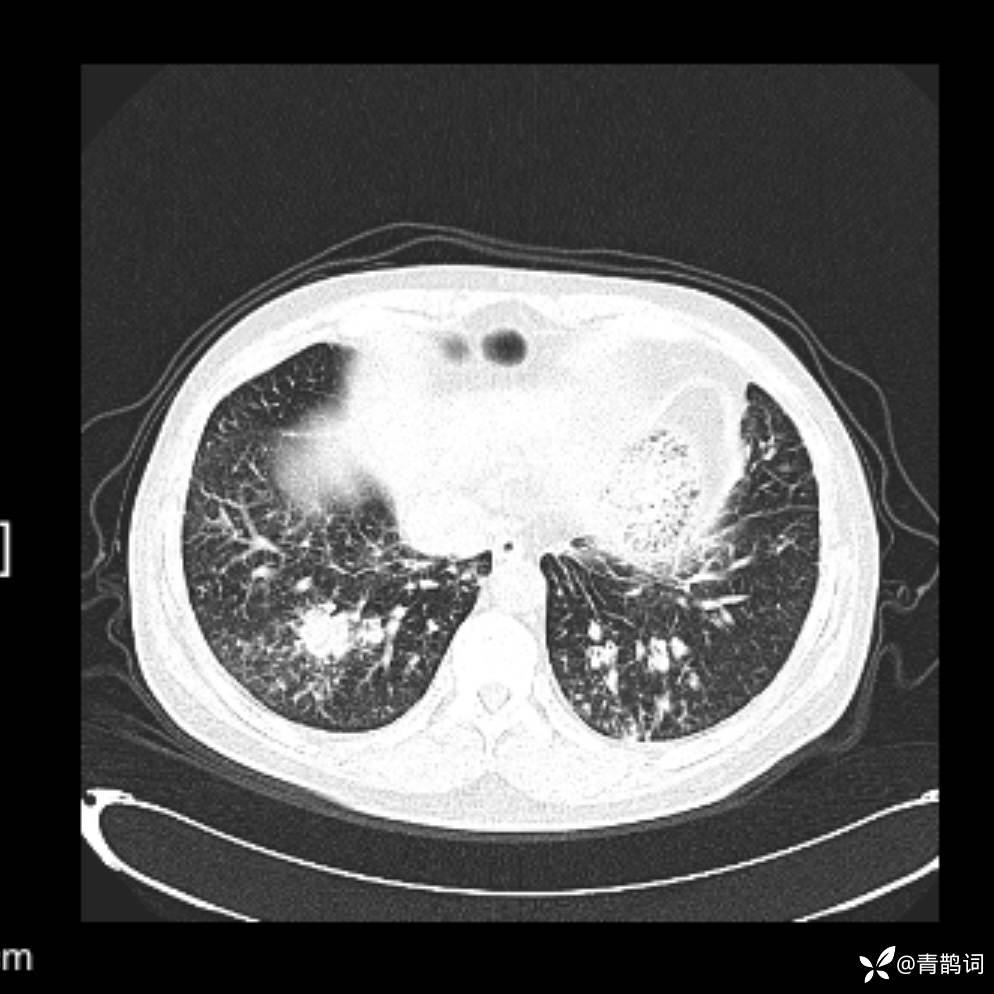

患者年龄:30岁。

患者性别:男。

简要病史:左颜面部肿胀2年,反复咳嗽咳痰,逐渐加重。

辅助检查